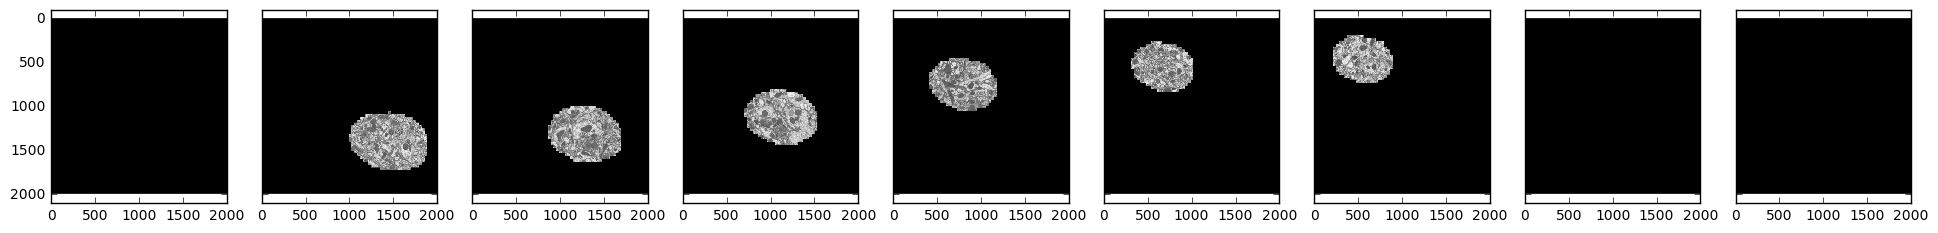

samples = [skimage.io.imread('http://emdata.janelia.org/api/node/bf1/grayscale/raw/xy/2000_2000/1800_2300_%d' % i)

for i in [1000, 2000, 3000, 4000, 5000, 6000, 7000, 8000, 9000]]

Sample electron microscopy images over time

We see that our field of interest wanders across the frame over time and drops off in the beginning and at the end.